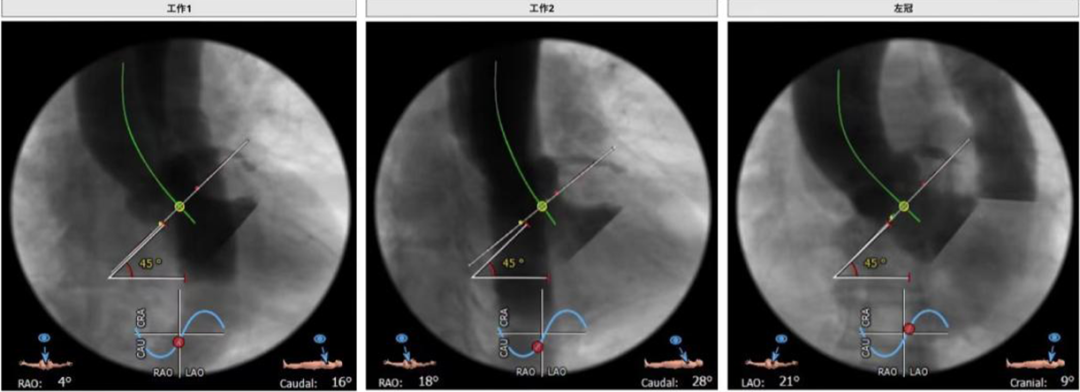

工作体位:RAO:4° CAU:16° RAO:16° CAU:28° 左冠:LAO:21° CRA:9°